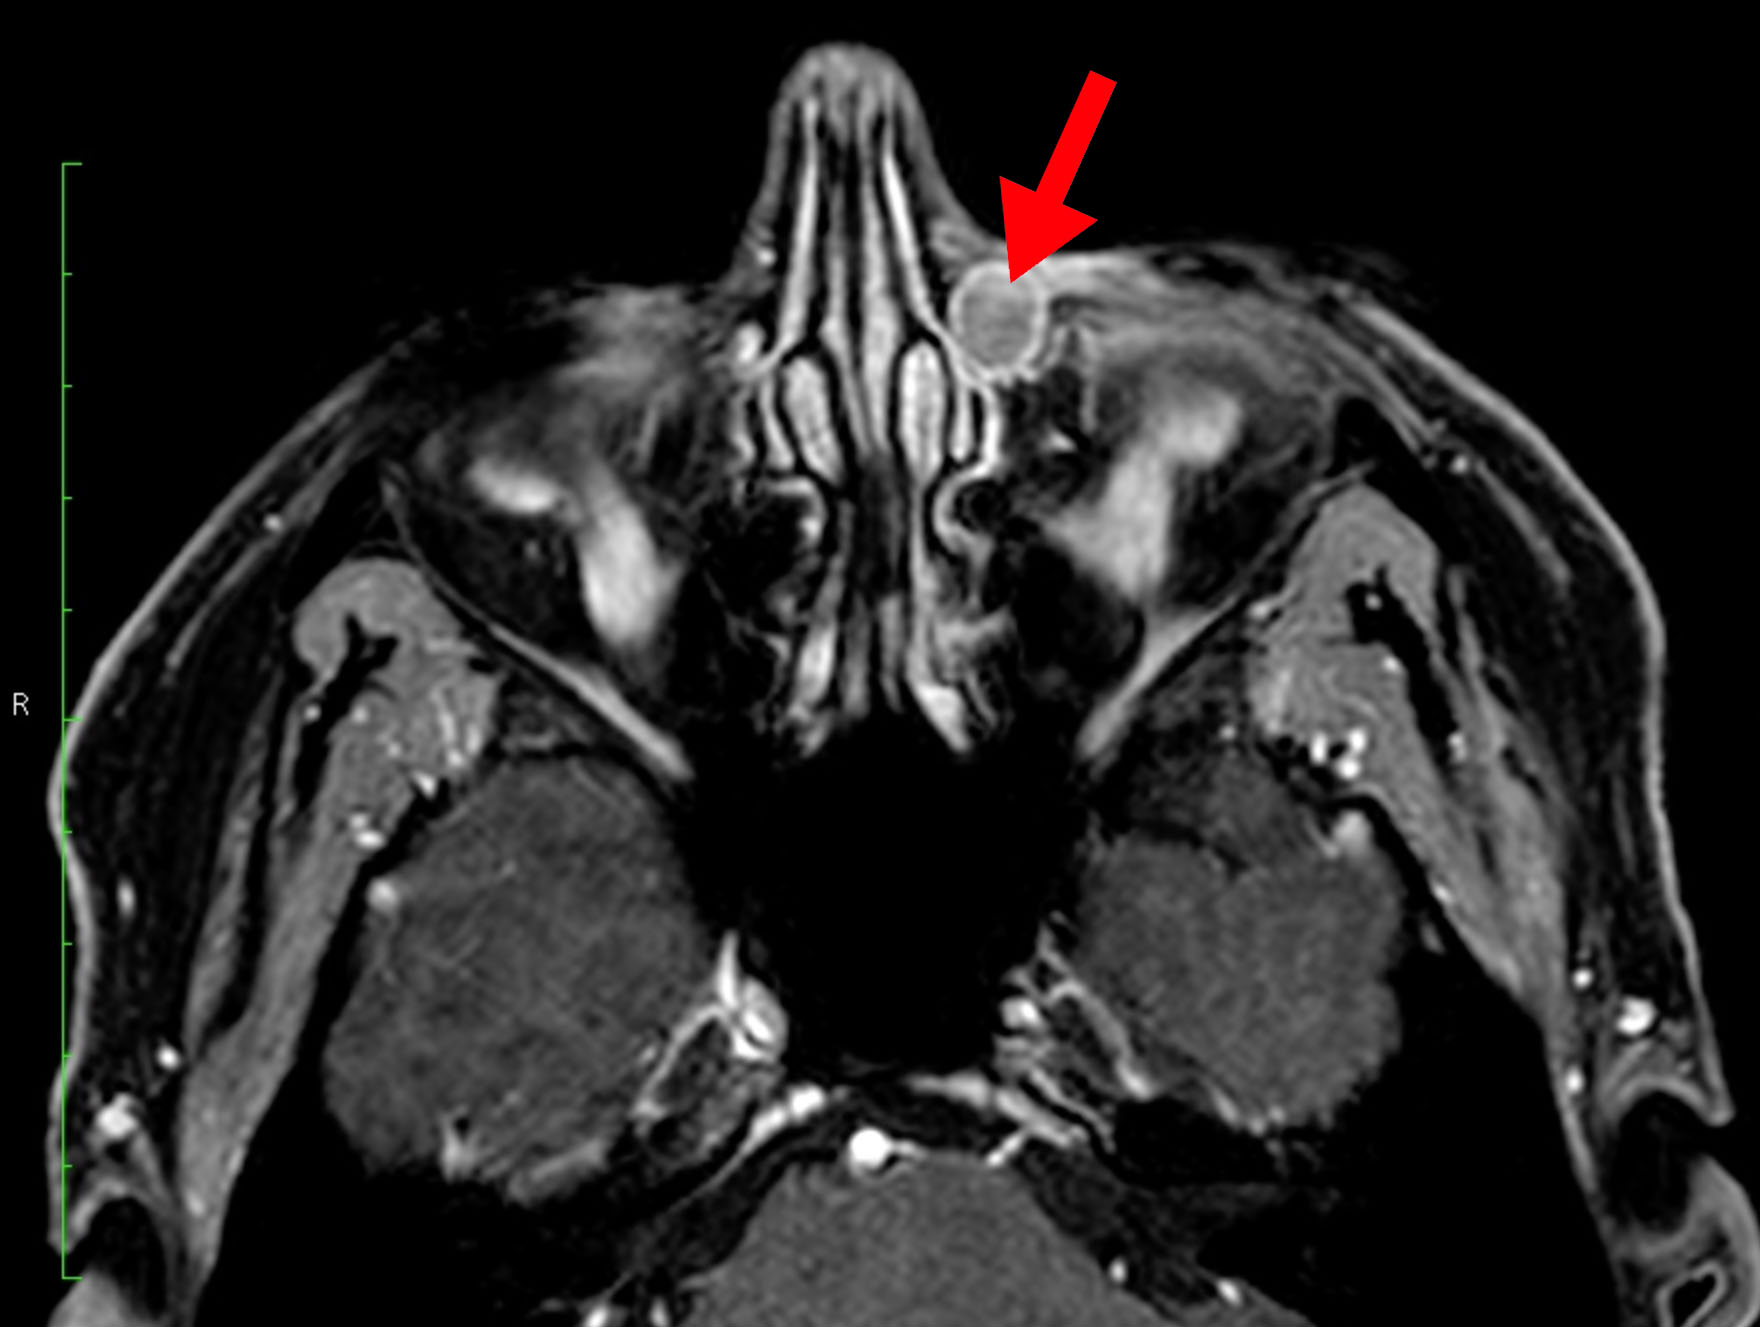

Clinical examination revealed a left-sided firm, well-defined lesion in the area of the lacrimal sac fossa. Lacrimal irrigation was suggestive of a partial nasolacrimal duct obstruction. The right-side examination was normal. Different modalities of imaging were performed, including dacryocystography (DCG), computed tomography dacryocystography (CT-DCG) and magnetic resonance imaging (MRI)(Fig.1).

Figure 1. MRI shows a well-defined lesion (cyst) in the left lacrimal fossa (red arrow)